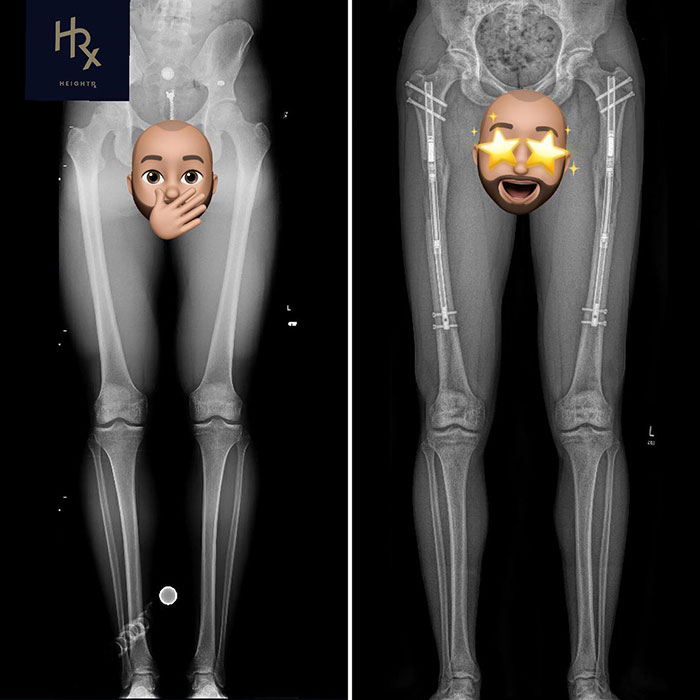

After the operations, during which Theresia’s bones were split and stabilized with metal rods, she suffered from bone infections twice.

The surgery itself consists of two main steps: An osteotomy, which means cutting the affected bone into two segments, and attaching a limb lengthening device to the two segments of bone.

The limb lengthening device can be an external fixator: the surgeon attaches a thin, light metal frame to the bones with pins or wires. The frame and most of the device are outside the body.

Or an internal rod: this newer option is a screw-like device that your surgeon places inside the bone. This device isn’t visible outside the body.

Specialists typically separate the bones by a total of one millimeter per day. If the patient has external fixators, the patient or a caregiver turns screws or dials on the fixator to achieve the required daily separation.